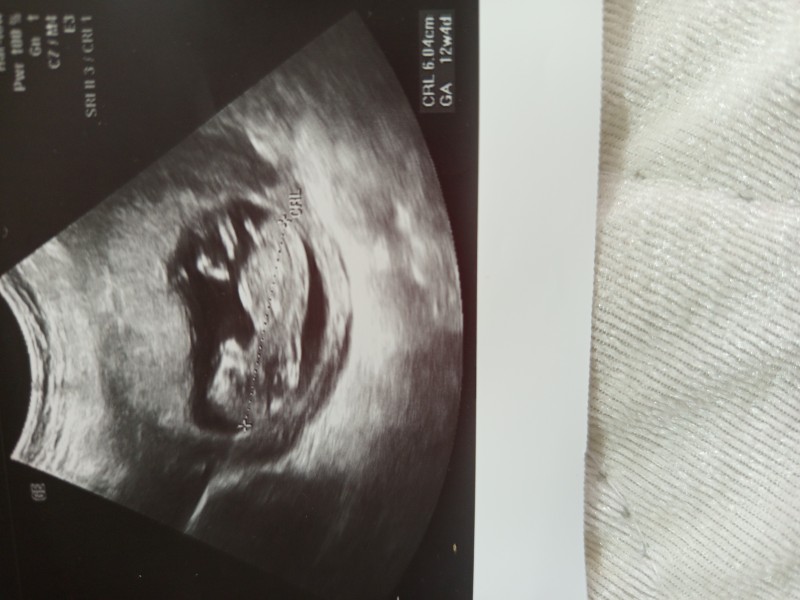

Doktor çok hareketli dedi emin olmadan soylemek istemiyorum dedi. Tahmin edebilecek olan var mı

Erkeğe benzettim

Erkek bence bu bebek

Erkek canısı

Teşekkür ederim yorumunuz için Özele de gittim işte doktor yine de söylemedi emin olmadan söylemek istemiyorum dedi merak ettim ben de sağlıklı olsun da cinsiyet fark etmez